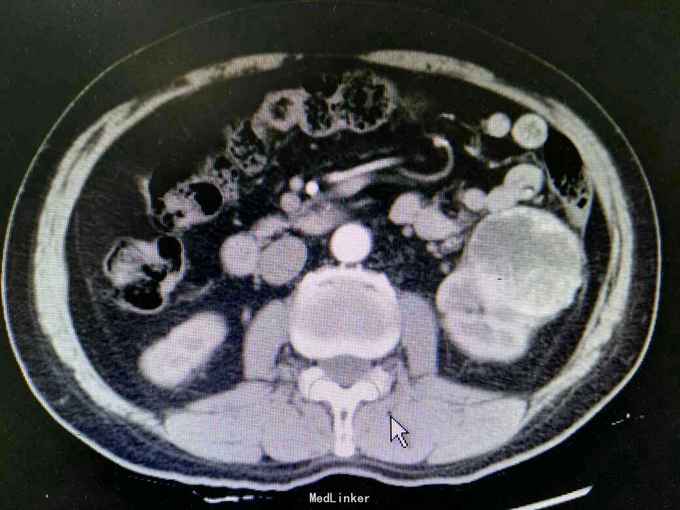

反复左腰酸痛不适5年,无血尿,无尿频尿急尿痛。外院B超:左肾囊肿。入院治疗。

体查未见明显异常。 CT:左肾外生性肿物,6.5x5.7cm,考虑肾癌 ECT:双肾功能良好。

诊断:左肾肿物 肾癌? 治疗:拟行腹腔镜左肾部分切除术。

讨论:肿瘤较大,适宜行部分切除还是根治性切除?